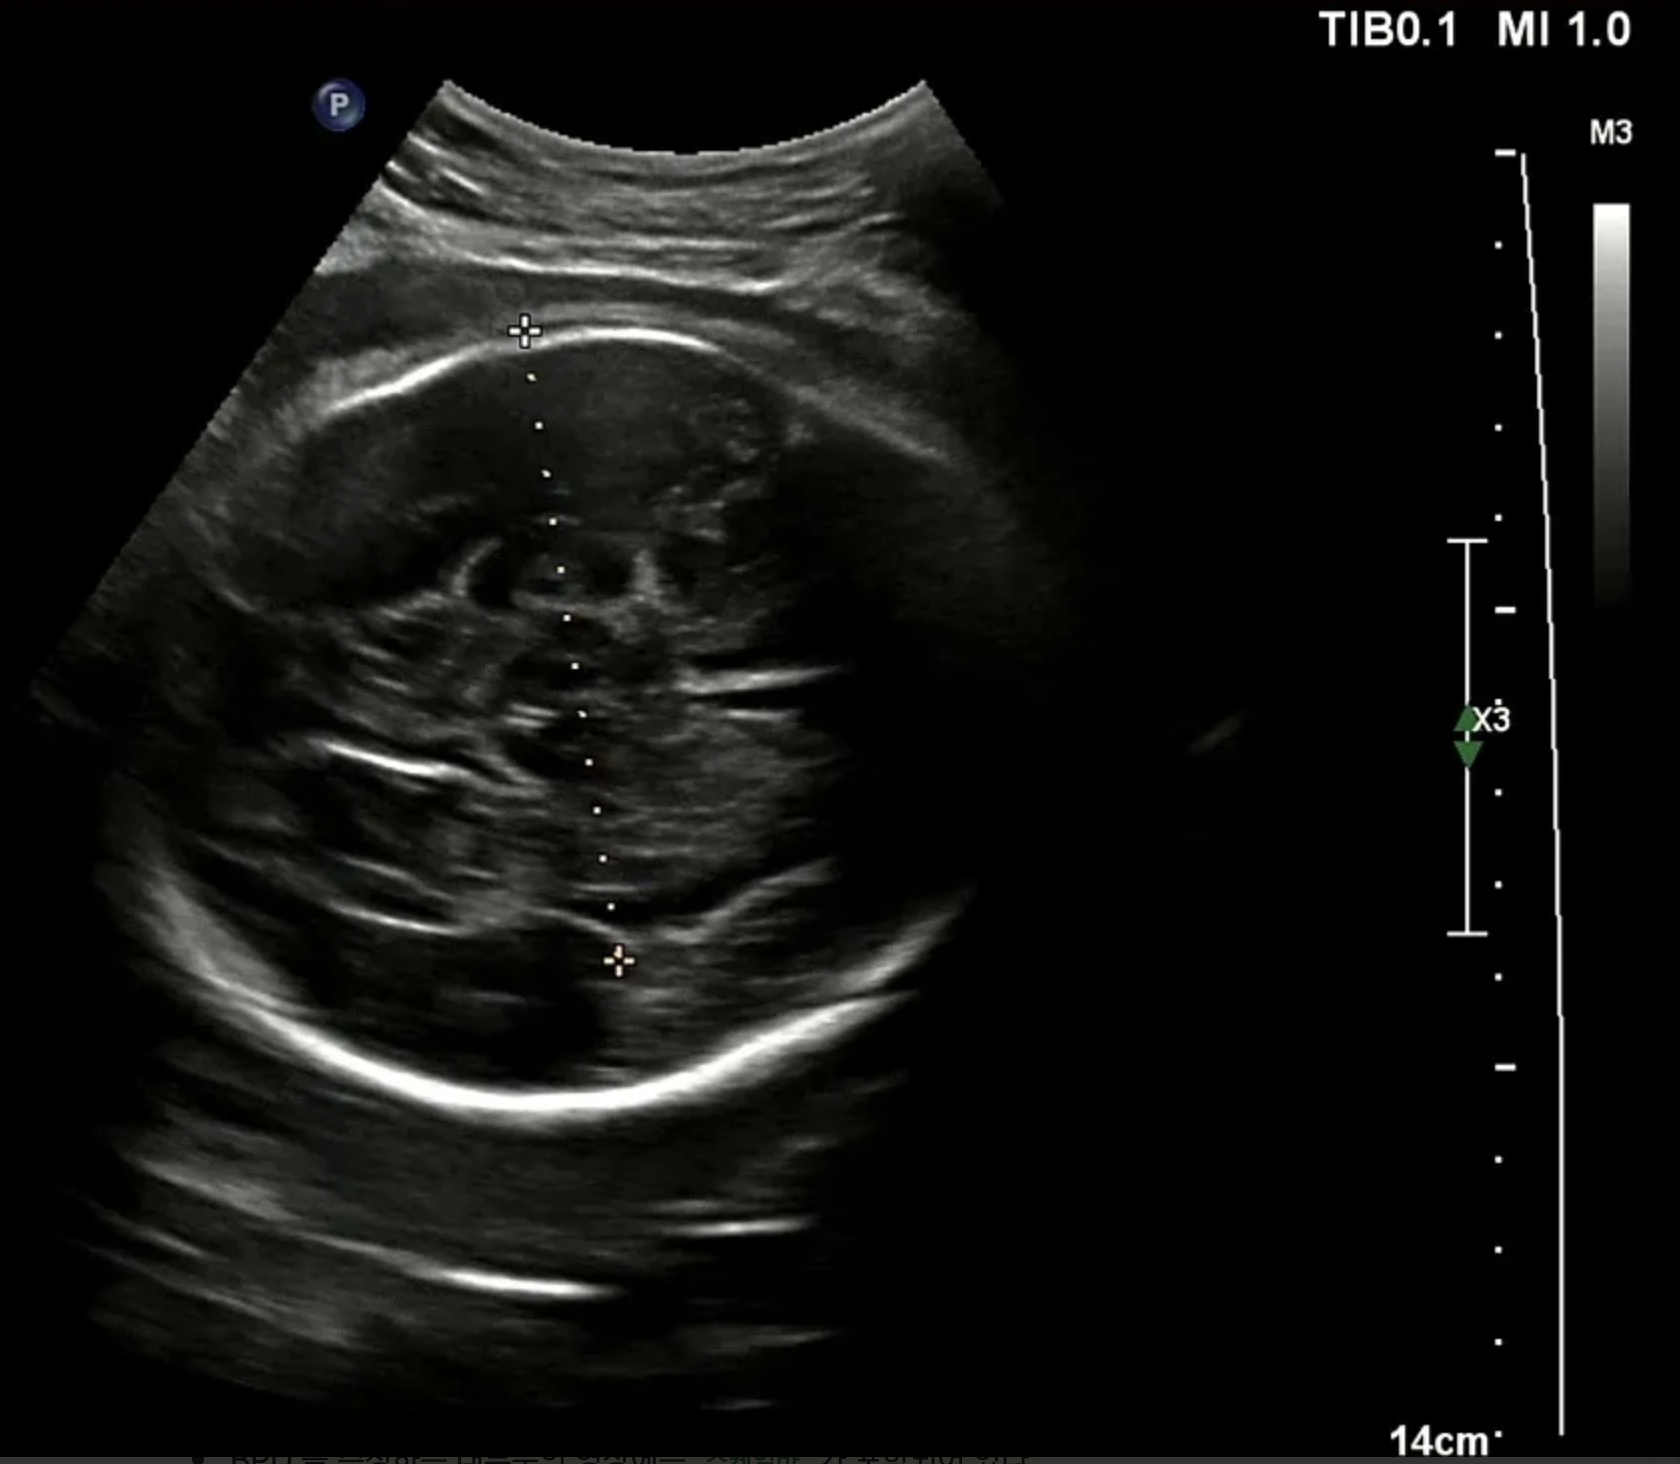

대부분의 녹화본에는 스케일바가 있다. 여기서 픽셀 당 실제거리 (cm/pixel) 을 구할 수 있다고 판단했다. 그래서 내가 원하는 두 점 사이의 거리 (단순 픽셀 거리) 곱하기 cm/pixel 을 곱하면 실제 거리를 구할 수 있다고 생각했다. cm/pixel 이 배율인 셈이다.

실제로는 8.22 cm 로 기록되었고 내가 측정한 기록값은 8.29 cm 로 오차는 크지 않았다. 가설을 검증했고 충분히 해볼 만하고 생각했다. 다만 아래와 같은 해결 과제가 남았다. 첫 번째는 계산 시 (14 cm / 스케일 바 픽셀 거리) 로 하드코딩해서 배율을 계산했기 때문에 스케일 바를 검출하는 이미지 전처리 과정이 필요했다. 두 번째는 초록색 영역 검출 시 곡선과 같은 형태 두 개를 찾고 그 사이 거리를 찾는 식이라 이미지별로 다소 편차가 있었다. 내 눈에는 원처럼 보이는데 컴퓨터가 인식할 때는 원으로 인식하지 않아서 반원 곡선 형태를 찾도록 코딩했다.